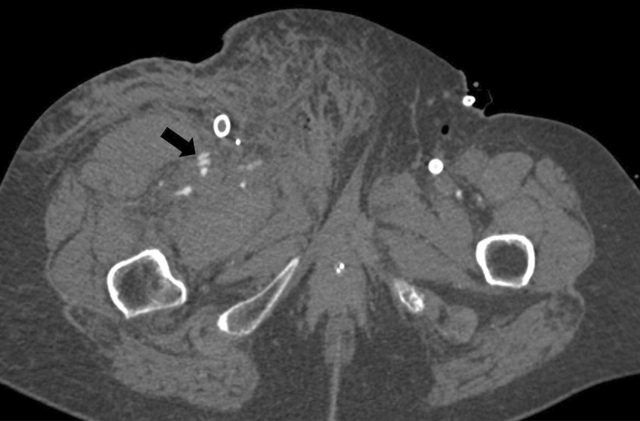

On the repeat CTA, the entire aorta was enhanced well (Figure 6), and a clear arterial contrast blush was observed originating from the superficial femoral artery and a side branch (Figure 7).

Figure 7

An axial image of a clear arterial contrast blush from the superficial femoral artery and a side branch.

The decision to briefly take off the ECMO and rely shortly on the cardiac output caused an arterial blush to emerge, thus enabling the demonstration of contrast extravasation with certainty and refer for targeted therapy.

In VA-ECMO, the peripheral placement of the ECMO-cannula provokes haemodynamic alterations with retrograde arterial blood flow, creating a watershed phenomenon at the level of flow collision. A watershed phenomenon can obscure active bleeding, thrombus, dissection or vascular occlusion. Adjusting the CT procedure to the clinical question is crucial for patients with an ECMO cannula. In this case, active bleeding of the superficial femoral artery became visible only after discontinuation of ECMO in the presence of a supporting multidisciplinary team.